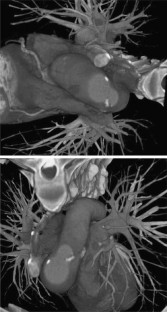

Fig 3.